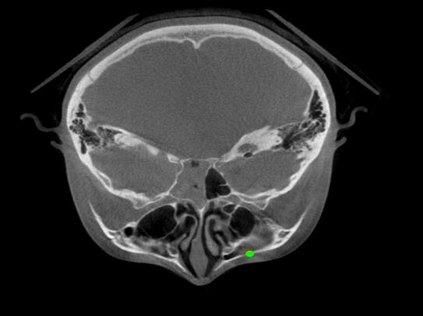

Detecting 3D landmarks on cone-beam computed tomography (CBCT) is crucial to assessing and quantifying the anatomical abnormalities in 3D cephalometric analysis. However, the current methods are time-consuming and suffer from large biases in landmark localization, leading to unreliable diagnosis results. In this work, we propose a novel Structure-Aware Long Short-Term Memory framework (SA-LSTM) for efficient and accurate 3D landmark detection. To reduce the computational burden, SA-LSTM is designed in two stages. It first locates the coarse landmarks via heatmap regression on a down-sampled CBCT volume and then progressively refines landmarks by attentive offset regression using multi-resolution cropped patches. To boost accuracy, SA-LSTM captures global-local dependence among the cropping patches via self-attention. Specifically, a novel graph attention module implicitly encodes the landmark's global structure to rationalize the predicted position. Moreover, a novel attention-gated module recursively filters irrelevant local features and maintains high-confident local predictions for aggregating the final result. Experiments conducted on an in-house dataset and a public dataset show that our method outperforms state-of-the-art methods, achieving 1.64 mm and 2.37 mm average errors, respectively. Furthermore, our method is very efficient, taking only 0.5 seconds for inferring the whole CBCT volume of resolution 768$\times$768$\times$576.